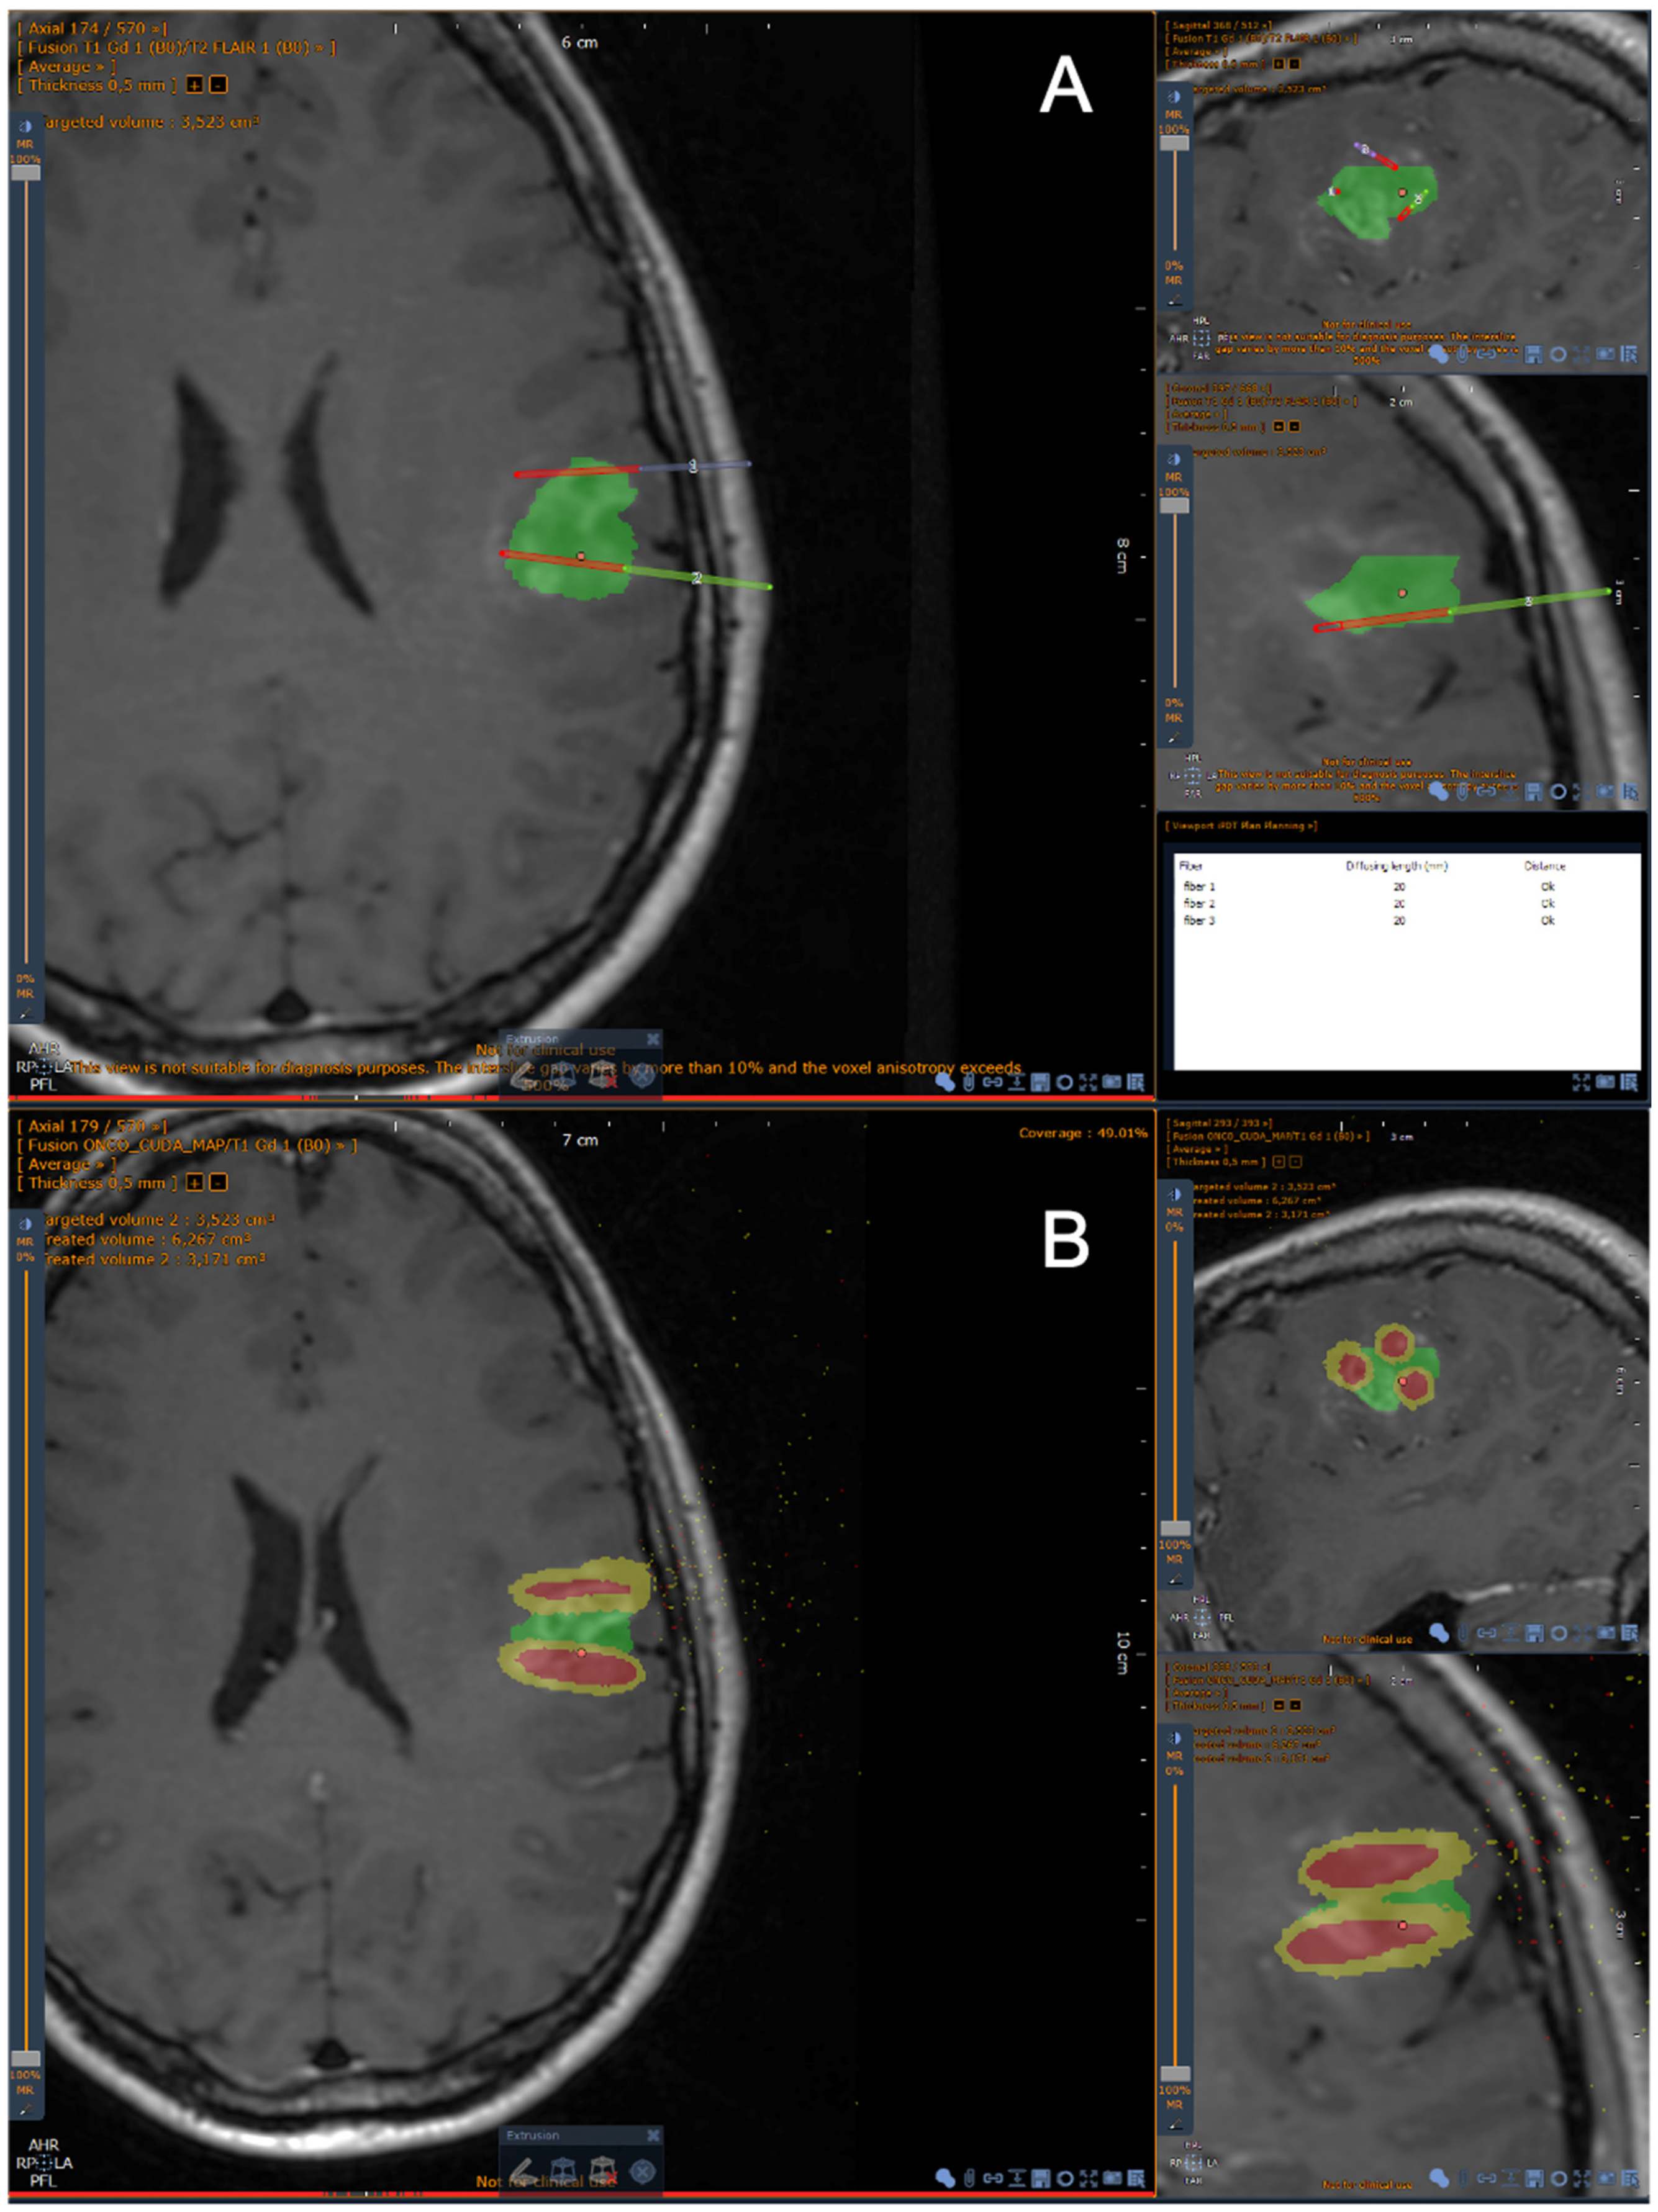

2.1. Planning Procedure

2.1.2. Segmentation Process

2.1.4. Optical Fibers Positioning

2.1.6. Monte Carlo Simulations

Specifications of the “Mcxyz” Program for Interstitial 5-ALA PDT